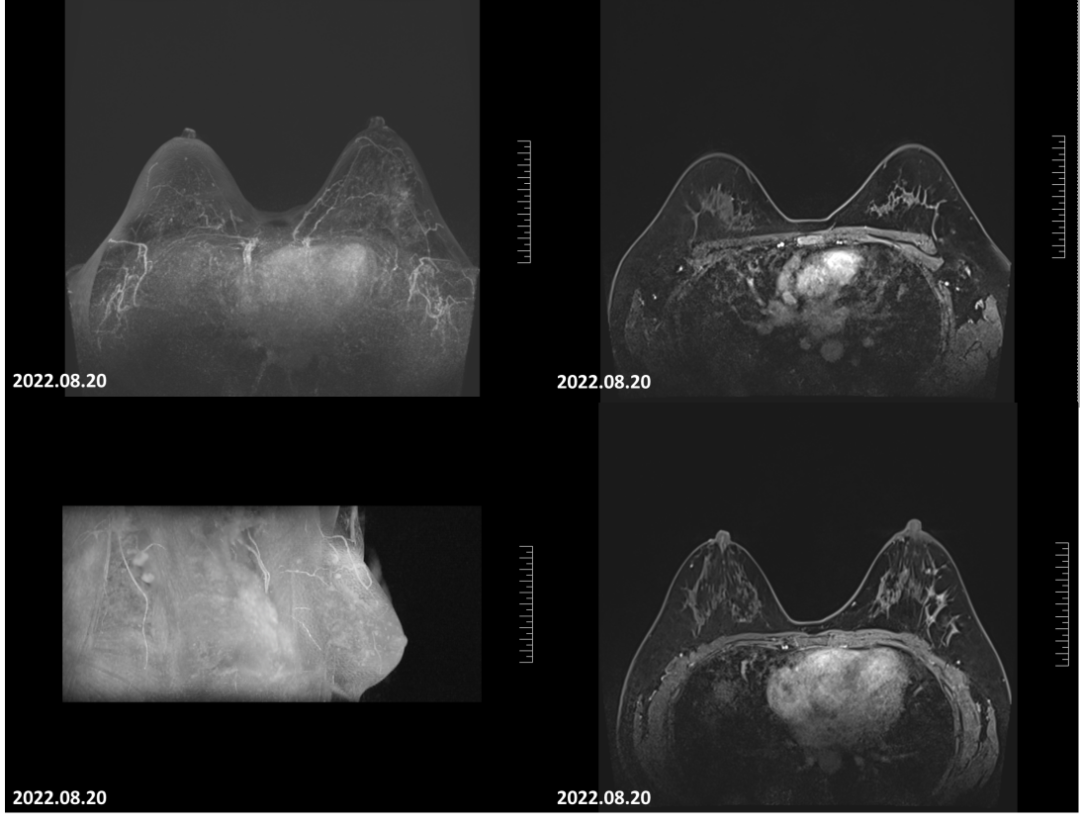

2022-08-20乳腺MRI报告:左乳上方可见点灶状强化,以左乳约3点钟方向稍明显,直径约4mm。大小约24mm×30mm×21mm(上下径×左右径×前后径),病变前缘距乳头约34mm,后缘距离胸壁约11mm。左侧腋窝淋巴结肿大,最大直径约7mm。

图6.4疗程后患者左乳肿物轮廓不明显,左乳肿物及左腋窝淋巴结均无明显增强。

2022-08-20乳腺超声:左乳可见多处低回声结节,较大者位于12点钟,大小约11mm×7mm×11mm,距体表10mm,距乳头35mm,形态不规则,边缘成角,内回声不均匀。CDFI:内可及点状血流信号。左侧腋窝可见数个淋巴结回声,髓质消失,较大者大小约12mm×8mm。CDFI:内可见点状血流信号。右侧腋窝及双侧锁骨上窝未见明显肿大淋巴结。

图8 4疗程后,患者左乳肿物核心基本消失,淋巴结缩小至正常大小。